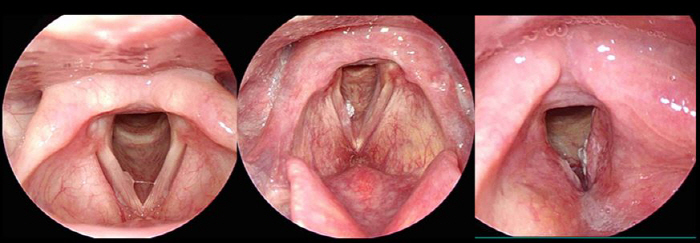

성대에 발생하는 후두암은 두경부암 중 가장 많이 발생한다. 물혹이나 바이러스에 의한 사마귀 조직과 다르게 단단하고 꽉 채워진 혹이 후두암이다. 후두암은 두경부암 중에서 가장 많이 발생하지만, 발생하면 바로 목소리가 변하고 전이 속도도 느린 편이기 때문에 치료 또한 가장 잘 된다. 목소리 변화가 6주 이상 지속된다면 후두암을 의심해 볼 필요가 있다.

두경부암이 의심될 경우, 먼저 내시경 검사를 통해 모양을 살펴보고 이후에 조직 검사를 해 확진을 한다. 확진이 되는 경우 CT나 MRI를 통해 범위를 확인하고 치료에 들어간다. 구강암의 경우는 수술이 일차적이며, 이 외에도 조기에 발견된 암은 하나의 치료 방법으로 단독 치료가 가능하다.